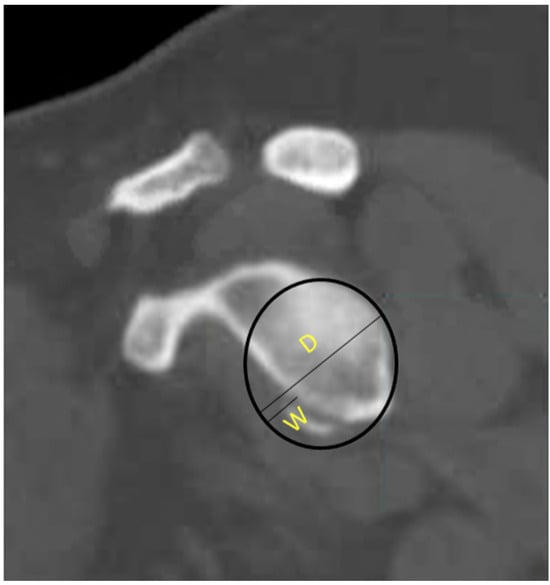

There is ample evidence that MRI is capable of quantifying the degree of glenoid bone loss [39]. Gyftopoulos et al. demonstrated that MRI could be accurately used to determine glenoid bone loss, with results comparable to CT and 3D CT [40]. Makovicka et al. recently proposed a new MRI-based technique for calculating glenoid bone loss. Instead of utilizing the borders of the glenoid to create a perfect circle, they suggested using two-thirds of the glenoid height to establish the diameter of a perfect circle of the glenoid (Figure 8). They found that this method produced similar results for the area of the perfect circle with superior reproducibility and consistency, allowing for a more objective assessment of glenoid bone loss [41]. MRI has also been able to identify on-track versus off-track Hill–Sachs deformities with a sensitivity of 72% and specificity of 88% [40]. Gyftopoulos et al. described a method of assessing glenoid bone loss utilizing the aforementioned circle method on 3D MRI. They found a direct relationship between the degree of glenoid bone loss and engaging Hill–Sachs lesions [42]. Stillwater et al. also demonstrated that 3D MRI achieved similar results in measuring humeral head loss, Hill–Sachs size, percent of humeral head loss, and percent of glenoid bone loss [43]. While these studies contained a limited number of participants, they suggest it may be possible to utilize 3D MRI in place of CT or 3D CT. This would help reduce the radiation exposure to patients and lower costs by requiring one fewer advanced imaging modality.

Figure 8. Two-thirds height perfect-circle method.